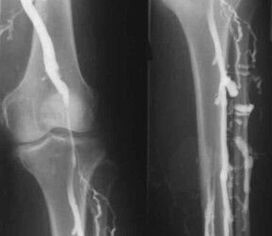

Ein erfahrener Phlebologe kann das Vorhandensein von Krampfadern in den tiefen Venen der unteren Extremitäten anhand charakteristischer Symptome feststellen, die selbst auf einem Foto der Beine deutlich sichtbar sind. Die Methoden zur Behandlung der Krankheit werden jedoch individuell nach einer detaillierten Untersuchung des Patienten und unter Berücksichtigung aller individuellen Merkmale seines Körpers ausgewählt.

Die gebräuchlichste instrumentelle Diagnosemethode ist die Ultraschalluntersuchung der venösen Gefäße der Beine. Mit dieser Technik können Sie das Gefäßsystem visualisieren und den Fortschrittsgrad des pathologischen Prozesses ermitteln.

1. Phlebographie.